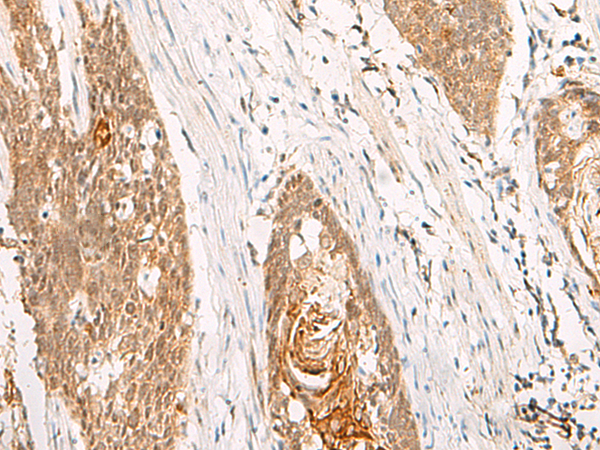

IHC positive control: |

Human esophagus cancer |

IHC Recommend dilution: |

50-300 |